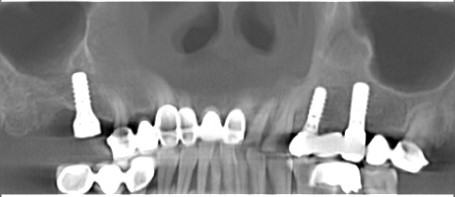

数字化种植导板引导下治疗流程

第一步:数据采集(口扫或仓扫+CBCT

第二步:数据匹配

(CBCT采集的Dicom数据与口扫获取的STL数据进行匹配,通过牙齿位点进行匹配。)

第三步:植入及导板设计

第四步:导板制作完成

(目前生成导板的方式主要有3D打印和切削两种方式)

第五步:外科手术

第六步:最终修复